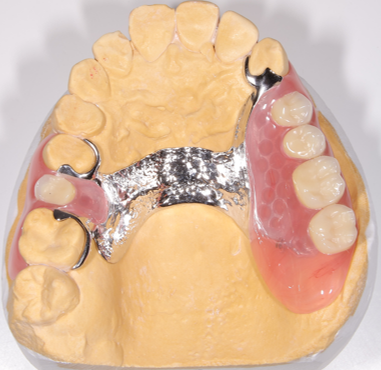

元々の義歯は緑線のように前歯の裏を通るように馬蹄型に設計されており、適合性や嚙み心地は問題なかったそうですが話しづらいのが気になっていたとのことでした。

欠損部が左右に跨るようにあり、欠損範囲も広いため左右別々の義歯は噛み心地と適合性が落ちるため、既存の義歯と同じように左右一体型の義歯を採用しました。ただ今までと同じ設計では話づらさが改善しないため今回は上顎の真ん中に薄い金属を通すことで違和感を極限まで減らす自費義歯を作成していくこととしました。

義歯は上顎の真ん中に薄い金属を通すことで話ずらさを改善しました。金属をたくさん使用していますが歯に引っかかる針金は歯茎の形をしているため見た目は義歯を装着しているようには見えません。適合性もばっちりとれています。